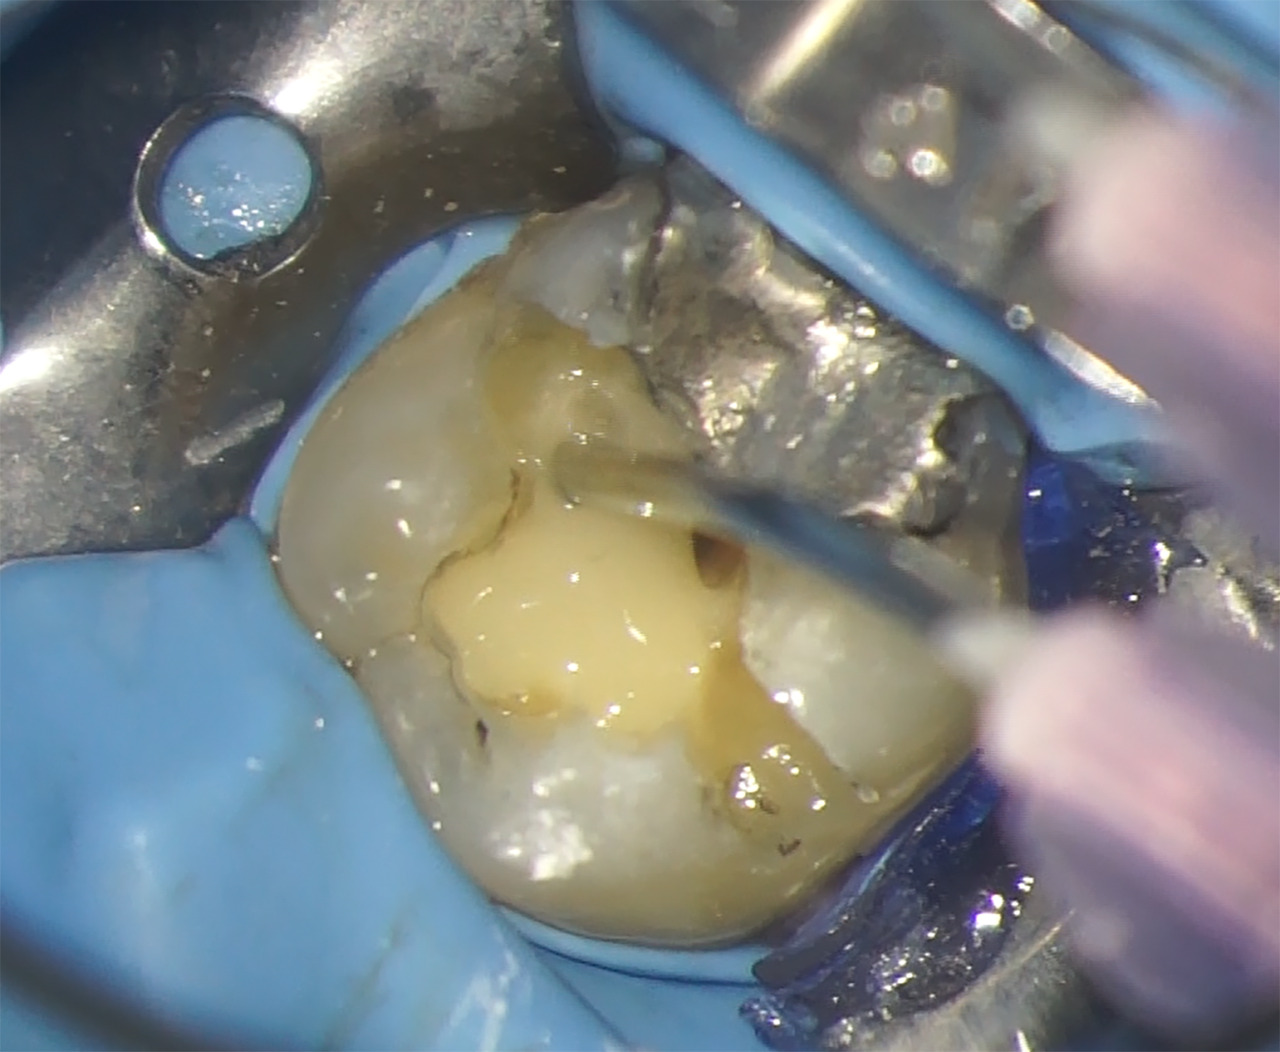

Réalisation de la cavité d’accès

Dans un premier temps, l’obturation à l’amalgame est éliminée en partie avec une fraise transmétal Talon 12 – (Tri Hawk, USA). Le reste de l’obturation sera éliminé lors de la confection de la restauration coronaire. Pour la cavité d’accès, il est décidé de réaliser une cavité de type Ninja qui permet d’accéder directement et uniquement au canal concerné (Fig.6).

Pour ce faire, la corne pulpaire mesio-vestibulaire et sa projection sur la face occlusale de la dent sont repérées sur l’image 3D issue de la segmentation. Cette trajectoire est mémorisée, et sert de guide pour le chemin de la fraise qui va permettre de réaliser une exposition pulpaire directe, franche et de petite taille.

La cavité est réalisée avec une fraise boule diamantée de diamètre 14 (Microcopy- USA) montée sur un contre-angle rouge utilisé avec un spray abondant.

Fig.6 : Vue occlusale de la dent avec la cavité d’accès réalisée.